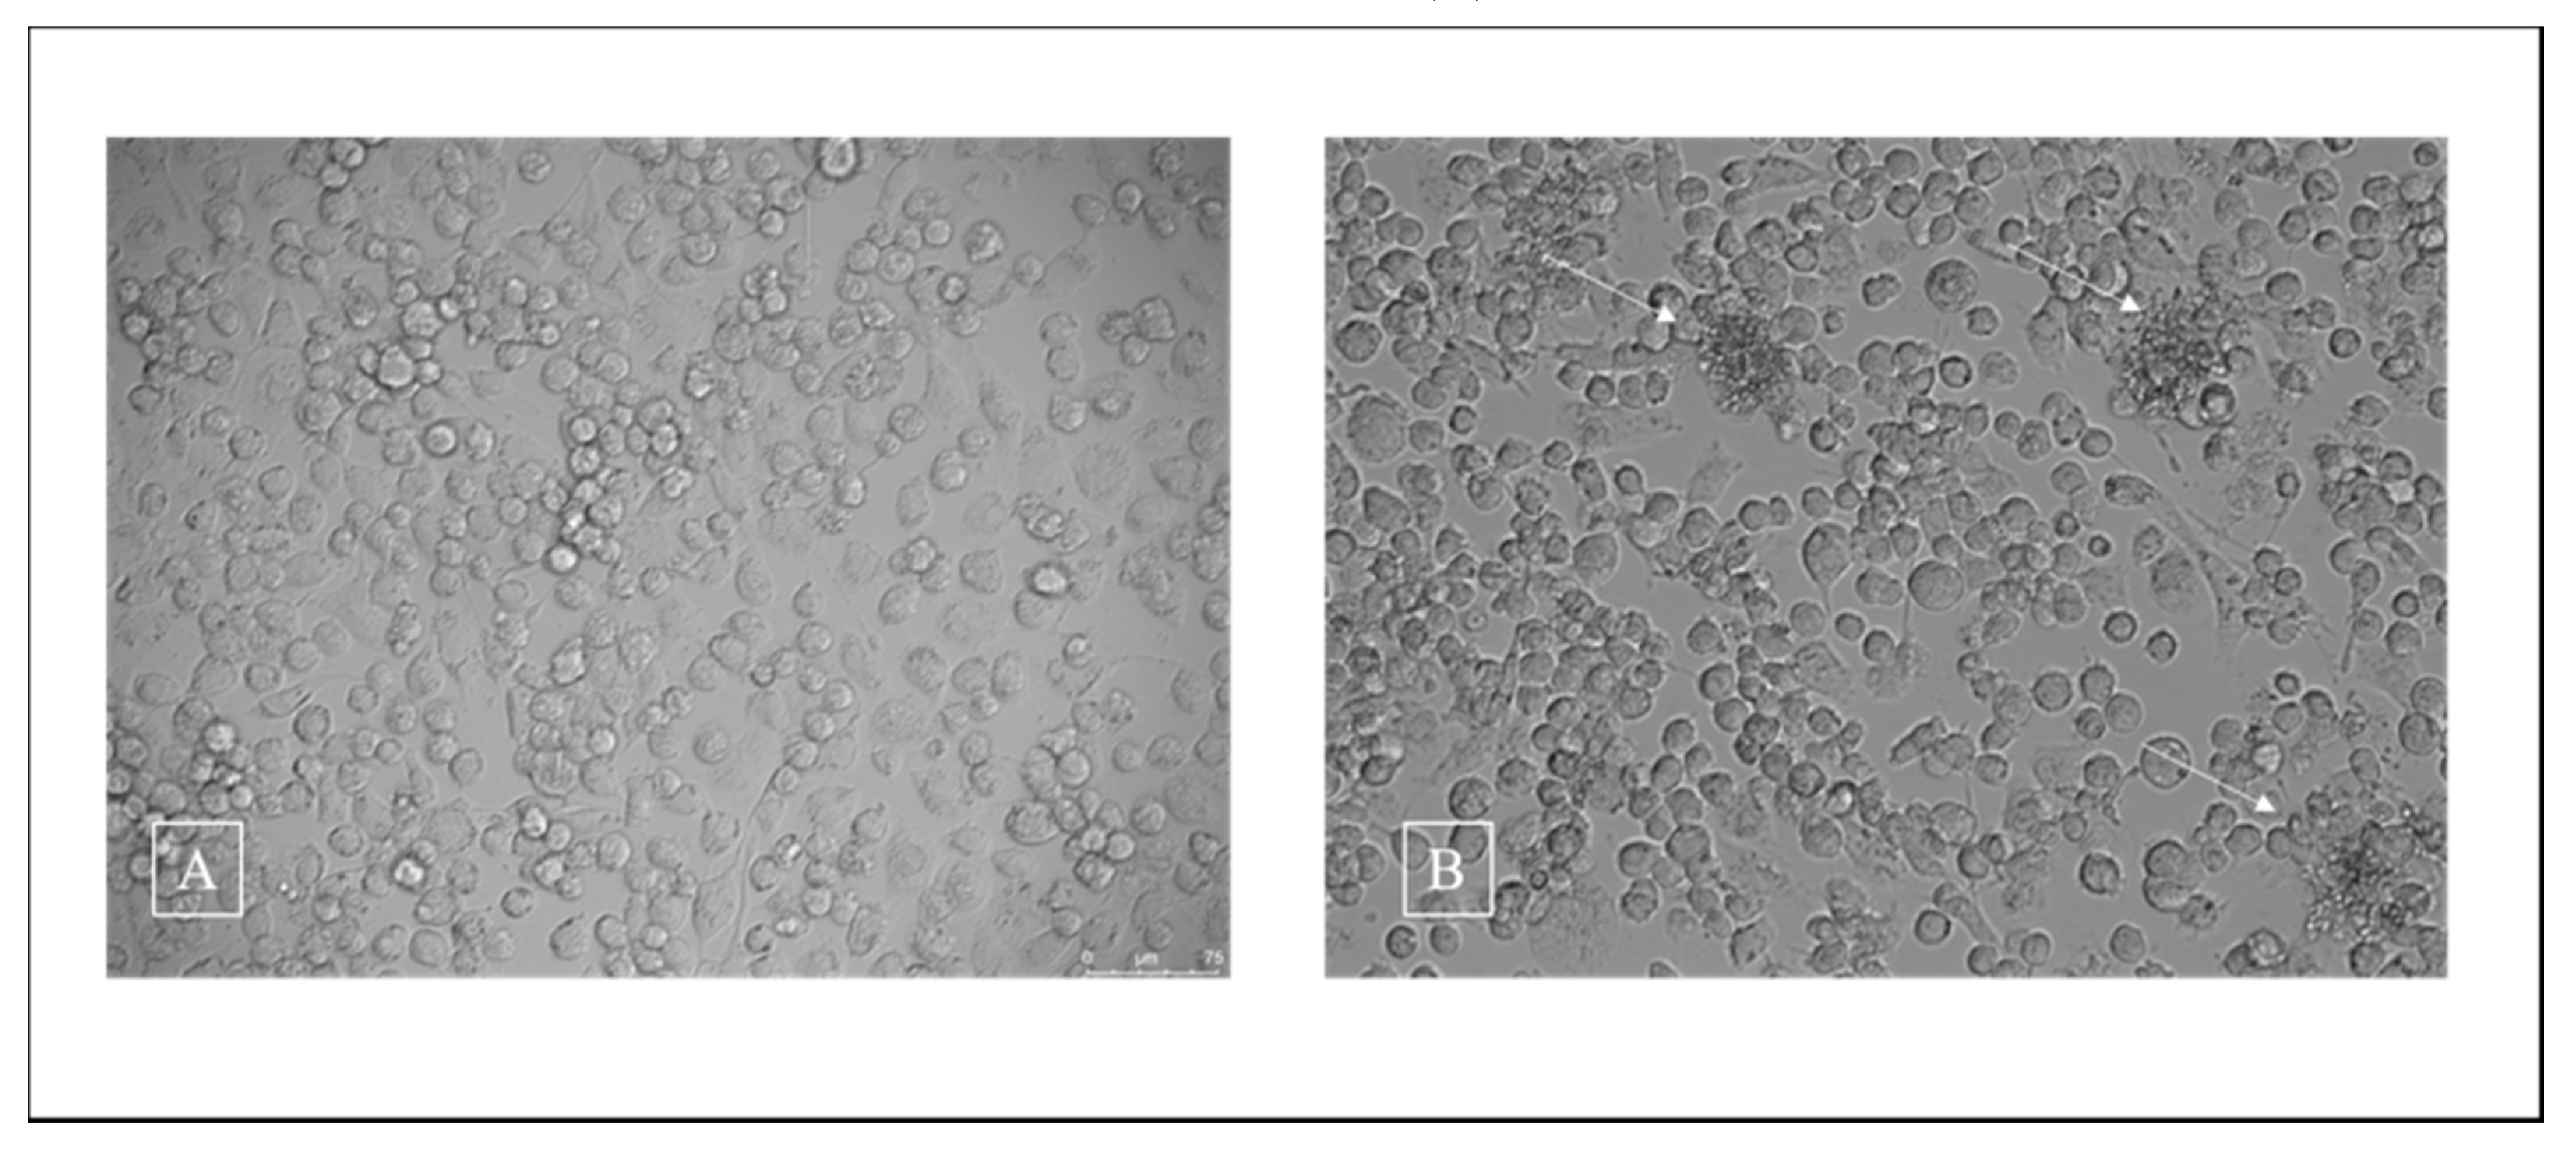

3.2. Cell Viability